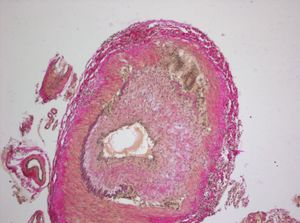

측두 동맥염을 진단하는 가장 확실한 방법(표준 진단법)은 측두동맥 생검이다.[22] 이는 국소 마취 하에 혈관의 작은 부분을 떼어내어 조직에 침투한 거대 세포가 있는지 현미경으로 검사하는 과정이다.

하지만 혈관 침범이 불규칙하게 나타나기 때문에, 병변이 없는 부위에서 조직을 채취하면 검사 결과가 음성으로 나올 수 있다(위음성). 따라서 생검 결과가 음성이라고 해서 거세포성동맥염이 아니라고 단정할 수는 없다. 일반적으로 1.5cm에서 3cm 길이의 조직을 한쪽에서 채취하며, 이 경우 진단 민감도는 85~90% 정도이다. 최소 1cm 이상의 길이가 필요하다.[23]

생검 조직에서는 혈관 중간층의 육아종성 염증, 내막 증식, 탄성판 파편화, 그리고 CD4 양성 T세포 침윤 등이 특징적으로 관찰된다. 이러한 병리학적 소견은 임상적 진단이나 다른 진단 기준들을 확증하는 데 중요한 역할을 한다.[11]